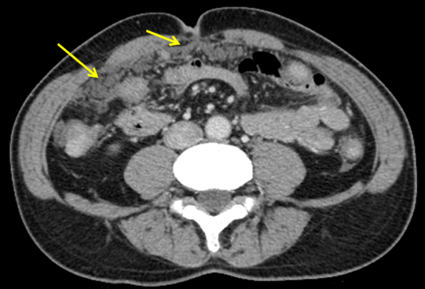

• ケーキ様大網

脂肪組織を主体とする腹膜の一部(大網)がケーキのように硬くなる様子を指します。

ケーキ様大網の様子